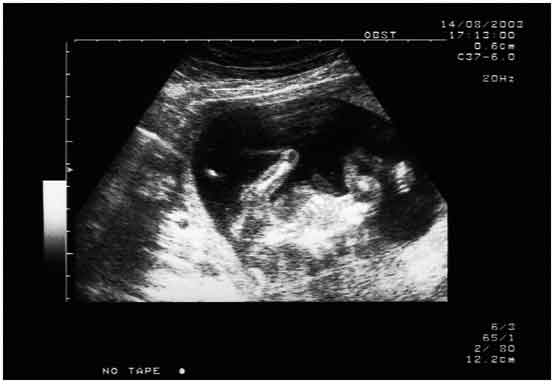

Gravidanza: nuovo test del sangue svela sesso nascituro al secondo mese

Sara’ maschio o femmina? Un semplice esame del sangue e’ in grado di fornire una risposta precisa gia’ alla settima settimana.

A parere dei medici, questa tipologia di test potrebbe rappresentare una svolta per le donne a rischio di avere bambini con determinate malattie legate al genere; in tal modo potrebbero essere evitate procedure particolarmente invasive, come per esempio l’amniocentesi. Ma lo studio solleva dei timori relativi all’uso dei test finalizzati alla selezione di genere. Anche se non ancora massicciamente prescritto da i medici statunitensi, il test del sangue per rilevare il sesso dei nascituri e’ stato finora venduto online. Le promesse di risultati accurati e in fase precoce hanno indotto i genetisti a fare delle analisi piu’ approfondite. Il test e’ in grado di rilevare il Dna fetale nel sangue della madri. Circa nel 95 per cento dei casi il test si e’ rivelato esatto, ma ovviamente la precisione del test aumenta con l’avanzare della gravidanza. Il test ha implicato l’utilizzo di una procedura di laboratorio chiamata Pcr, in grado di rilevare il materiale genetico presente nel siero: nel caso in cui il cromosoma Y maschile risulta presente nel sangue della madre, allora si tratta di un maschio; se e’ assente, di una femmina. Lee Shulman, capo della genetica clinica presso la Northwestern Memorial Hospital di Chicago, ha detto che il test “non e’ ancora pronto per il debutto”. “Avrei un sacco di difficolta’ – ha inoltre aggiunto – a offrire una prova solo per l’identificazione del genere. Il sesso non e’ un’anomalia”.